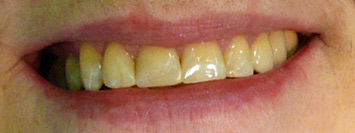

poslije